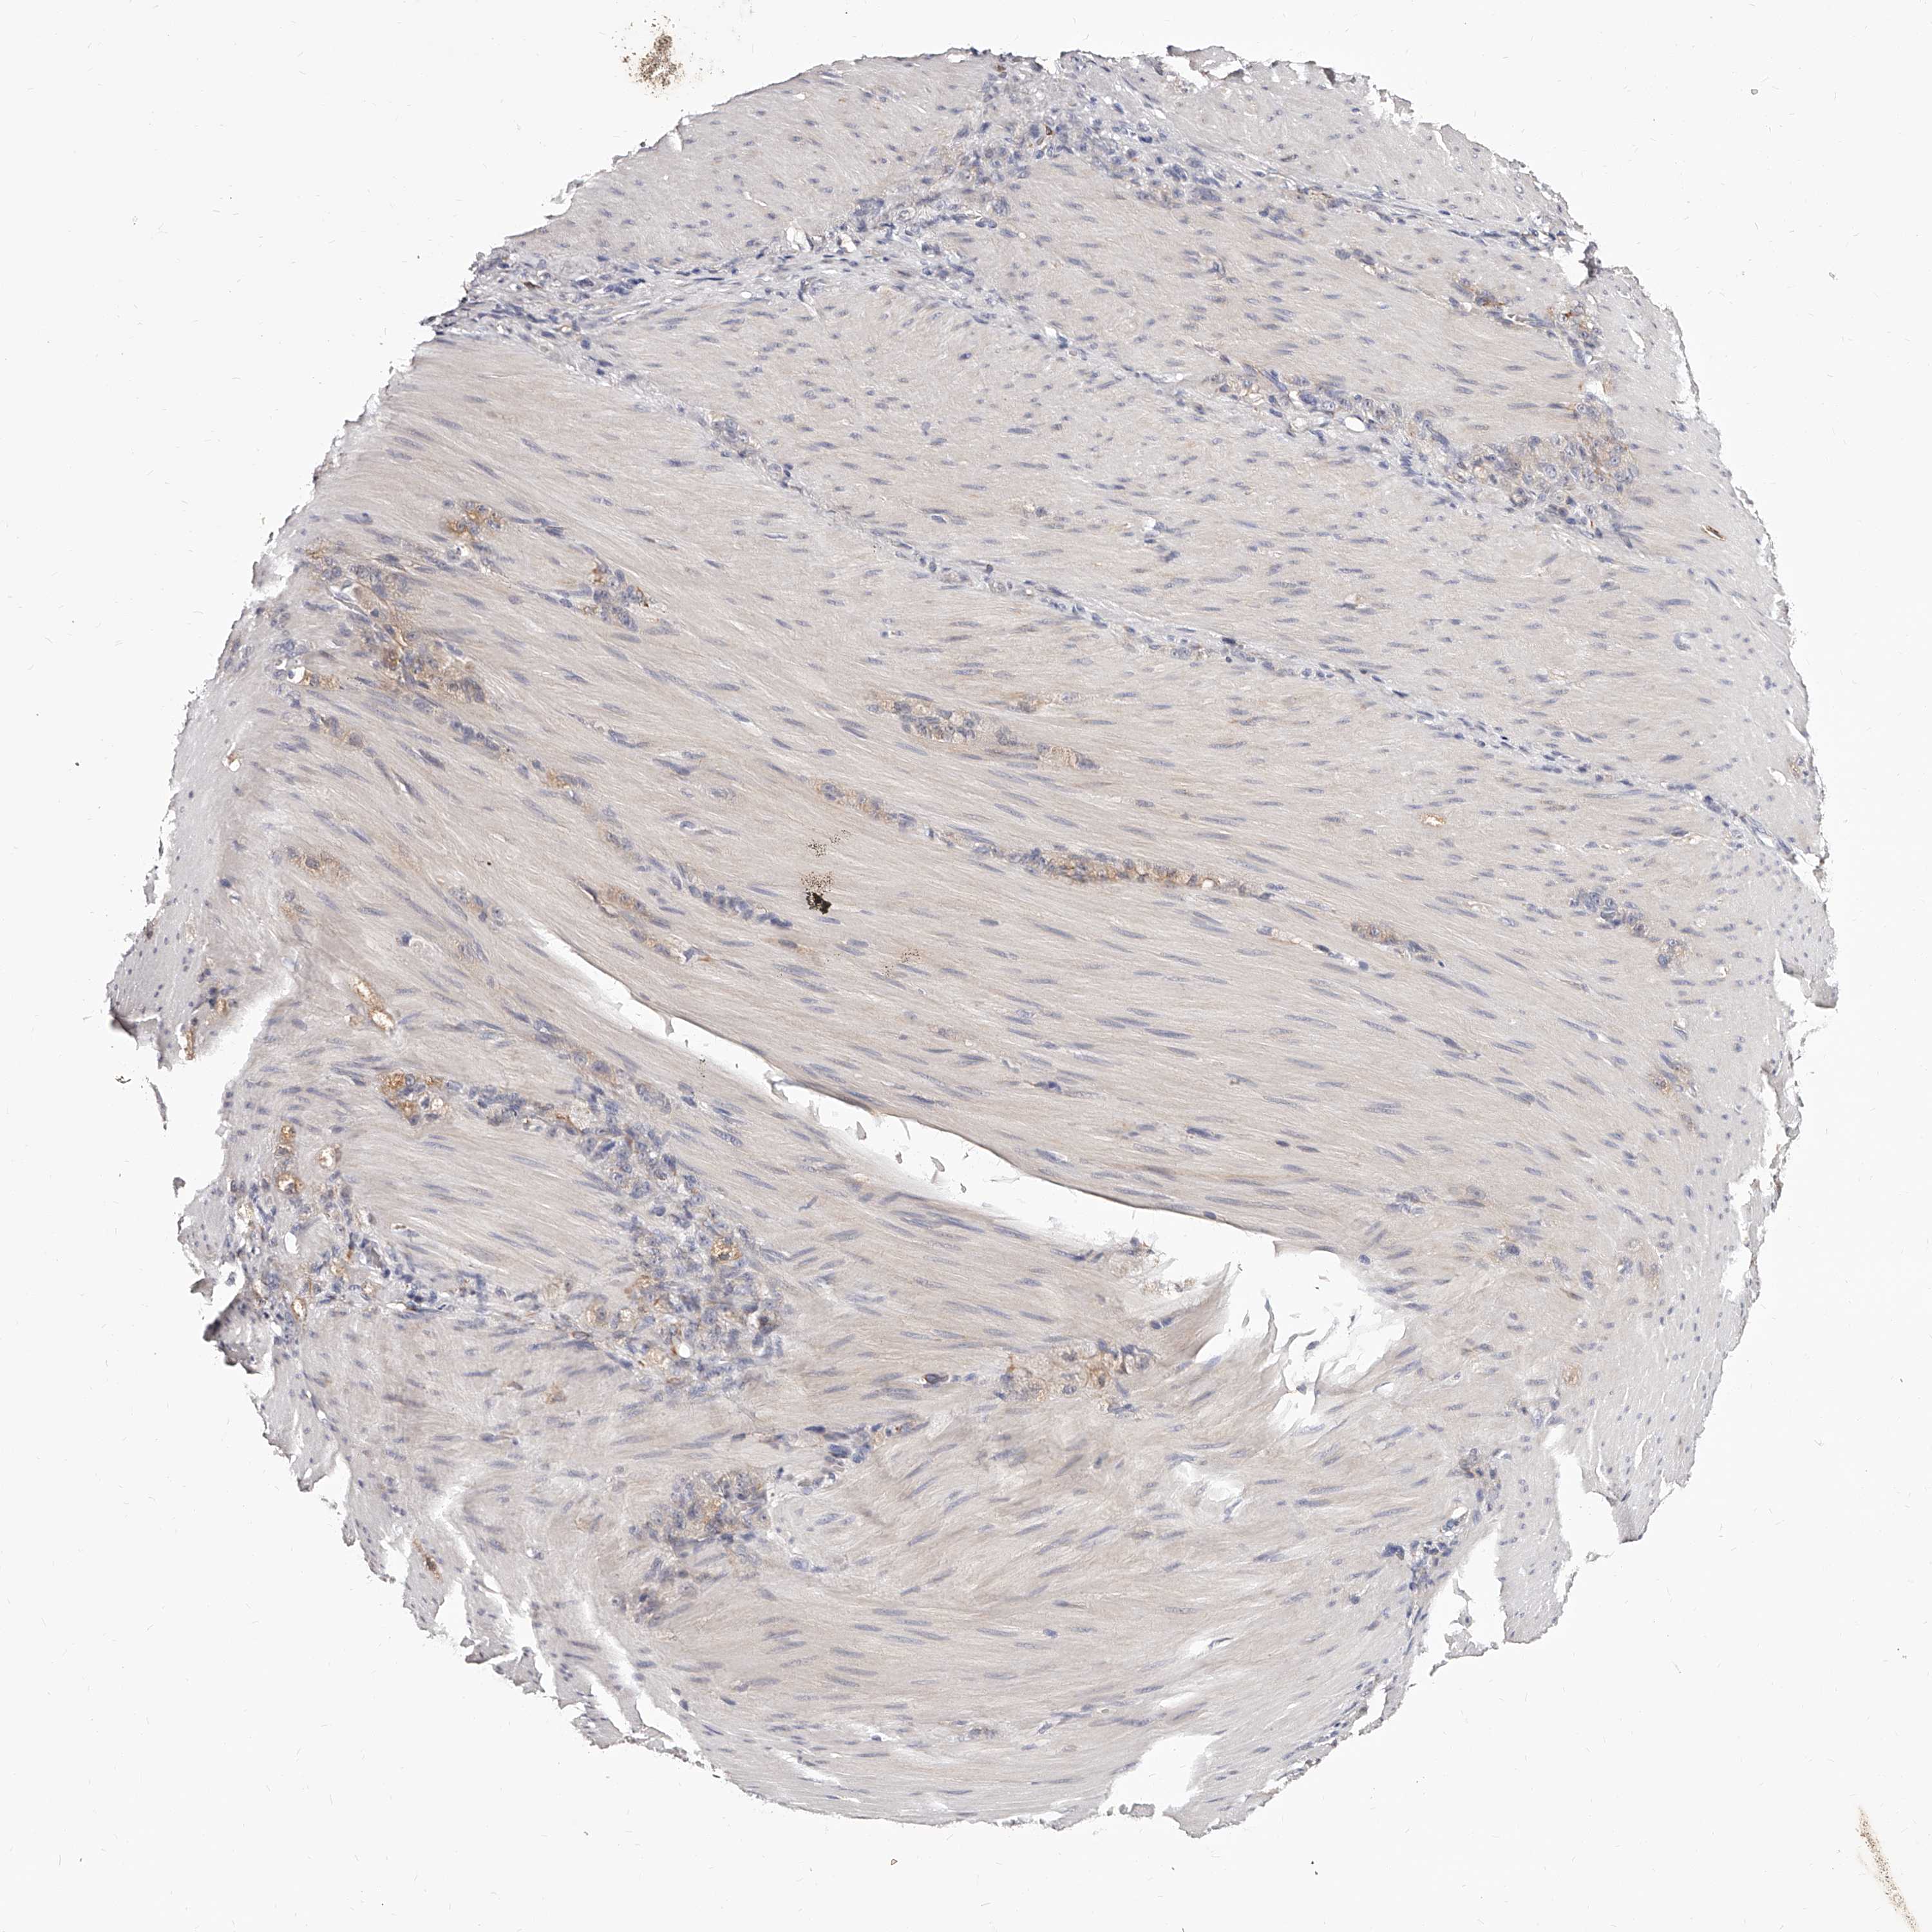

STOMACH CANCER - Protein expressioni

A mouse-over function shows sample information and annotation data. Click on an image to view it in a full screen mode. Samples can be filtered based on level of antibody staining by selecting one or several of the following categories: high, medium, low and not detected. The assay and annotation is described here.

Note that samples used for immunohistochemistry by the Human Protein Atlas do not correspond to samples in the TCGA dataset.

Antibody stainingi

Antibody staining in the annotated cell types in the current human tissue is reported as not detected, low, medium, or high, based on conventional immunohistochemistry profiling in selected tissues. This score is based on the combination of the staining intensity and fraction of stained cells.

Each image is clickable and will lead to virtual microscopy that enables deeper exploration of all samples and also displays staining intensity scores, fraction scores and subcellular localization as well as patient and tissue information for each sample.

Adenocarcinoma, NOS